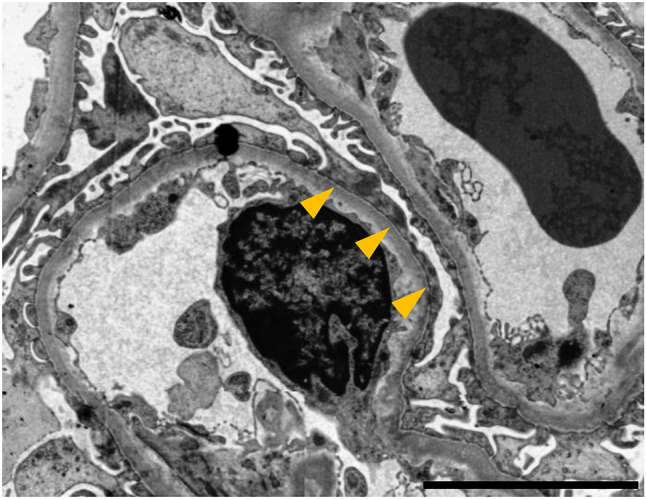

Among the 26 glomeruli retrieved via percutaneous renal biopsy, histopathologic findings include global sclerosis in 6 glomeruli, segmental sclerosis in 3 glomeruli, and adhesion in 2 glomeruli. Others exhibited glomerular hypertrophy (the maximum diameter; 250 μm) with mild mesangial cell proliferation. Moreover, tubular atrophy with interstitial fibrosis and inflammatory cell infiltration was observed in 50% of the renal cortex. Arteriolar wall thickening was also identified (Fig. 2). Immunostaining for immunoglobulins and complement proteins showed negative or non-specific deposition. Electron microscopy revealed the foot process effacement of podocytes and widening of the subendothelial spaces (Fig. 3). These findings were consistent with a diagnosis of FSGS, not otherwise specified.

Fig. 3.

The findings of electron microscopy. The foot process effacement of podocytes (arrowheads) is observed in electron microscopy study. Scale bar indicates 5 µm